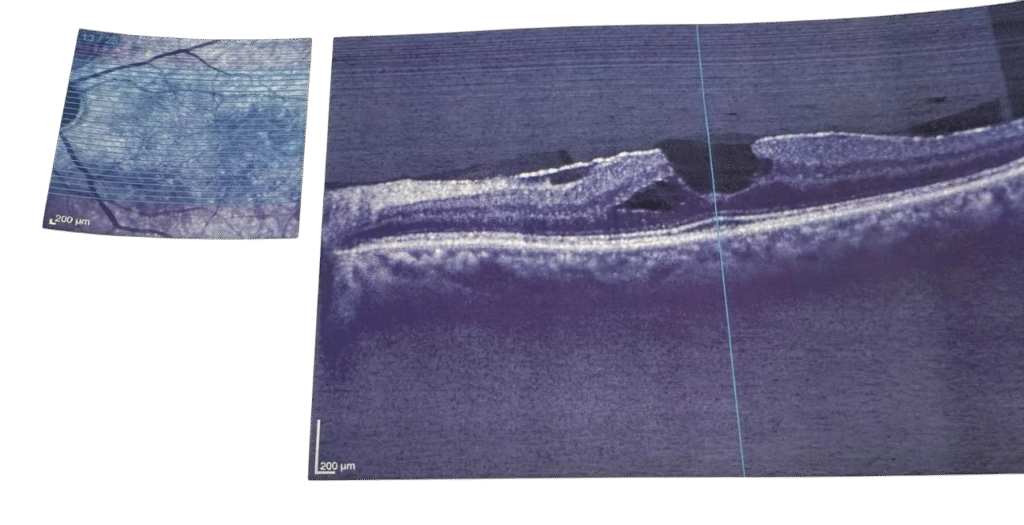

Resim 1: Epiretinal öncesi

Resim 2: Epiretinal sonrası